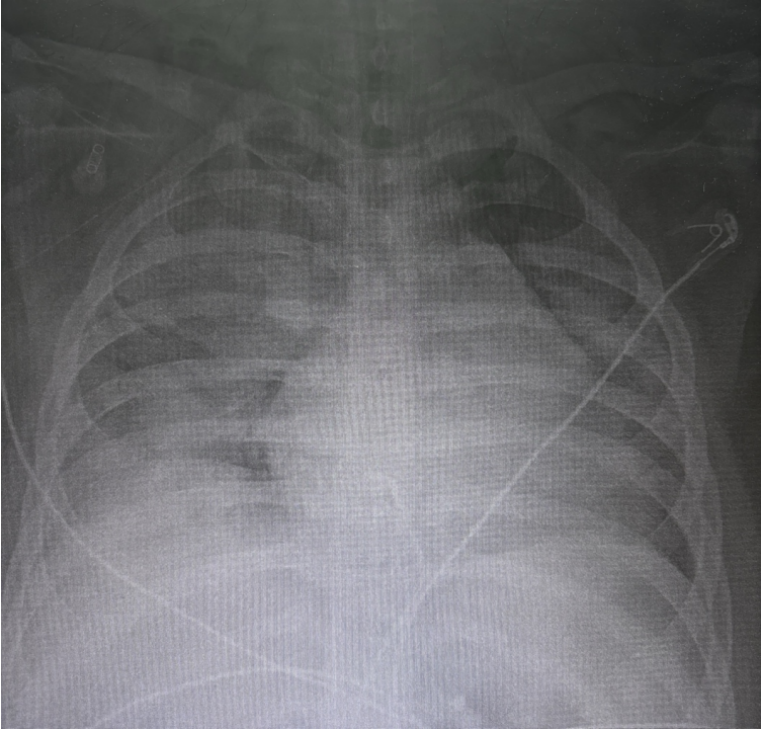

患者入科5天后复查胸片发现病变较前明显改善,肺容积明显增加,炎性渗出较前减少(图8)。感染指标整体下降,无发热(图9)。液体出入平衡(图10),循环稳定。

图片

8   复查患者胸片(2024-01-26)